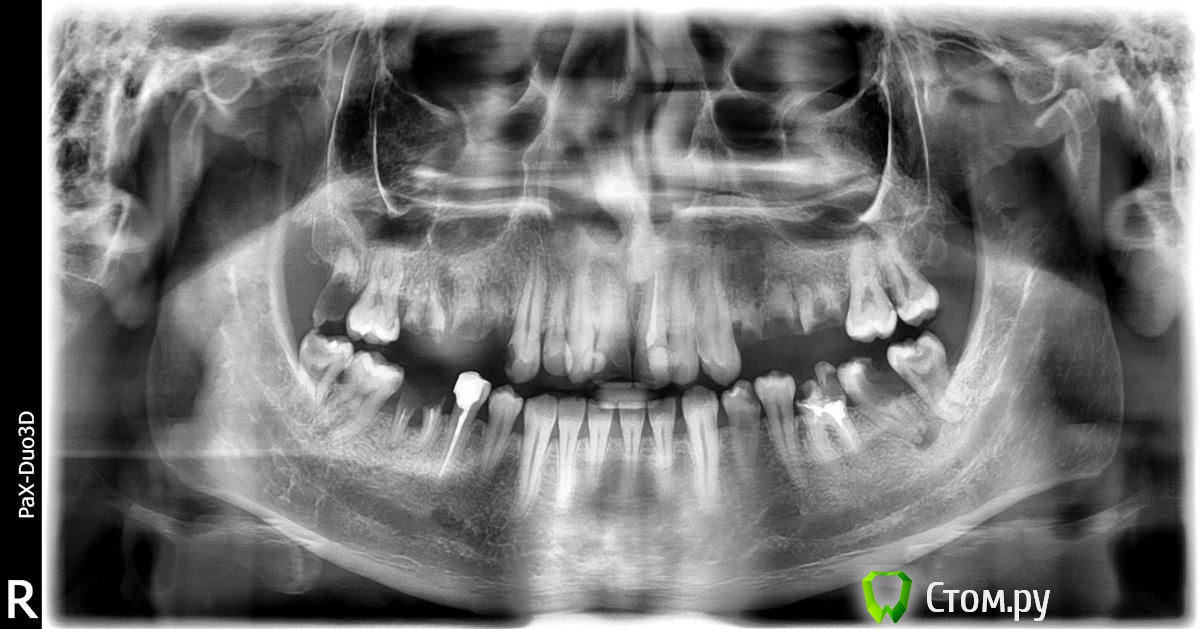

П. С. Вот мой снимок после первого посещения.

удаление 18, 16, 15, 14,24,25,26,28,38,37, 36(?), 46, 48.

36(?) - перелечивание и под коронку. 45,21 - коронки.

Лечение кариеса.

имплантаты в позиции 16, 15?, 14, 24, 25?, 26, 37, 36(? - если зуб придется удалить), 46.